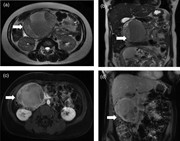

Left adrenal tumor extending into the renal vein: surgical management with ipsilateral kidney preservation

Arnaud Doerfler and others

Journal of Surgical Case Reports, Volume 2015, Issue 8, August 2015, rjv098, https://doi.org/10.1093/jscr/rjv098